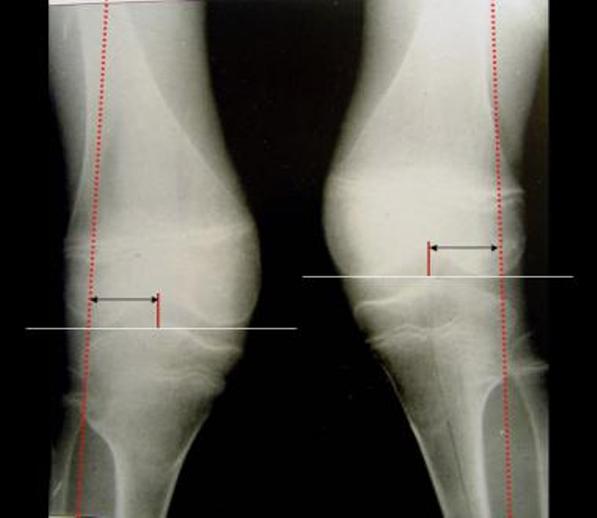

Medical Term Knock Knees . Knock knees (genu valgum) is a condition in which the knees tilt inward while the ankles remain spaced apart. The condition is slightly more common in girls, though boys can develop it too. It appears most frequently in young children. Knock knees is when there's a gap between your ankles when you stand with your knees together. It's common in children aged 3. Knock knees are condition in which the knees touch, but the ankles do not touch.

Knock knees is when there's a gap between your ankles when you stand with your knees together. The condition is slightly more common in girls, though boys can develop it too. It's common in children aged 3. It appears most frequently in young children. Knock knees (genu valgum) is a condition in which the knees tilt inward while the ankles remain spaced apart. Knock knees are condition in which the knees touch, but the ankles do not touch.